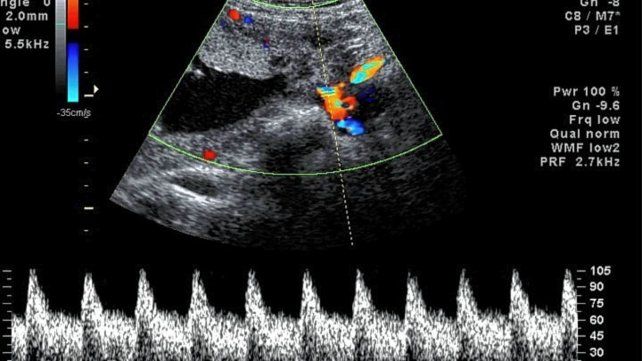

El control. Durante el embarazo es importantísimo, ya que las cardiopatías se desarrollan y se pueden detectar a partir de la 8ª semana del embarazo.

Desde la institución hicieron saber que el control durante el embarazo es importantísimo, ya que las cardiopatías se desarrollan y se pueden detectar a partir de la 8ª semana del embarazo.

El diagnóstico exacto se hace a través del ecocardiograma (sumado al examen del médico y otros estudios como el electrocardiograma) y el tratamiento está a cargo del cardiólogo infantil.

“Los avances en el diagnóstico prenatal y en las cirugías permiten intervenciones más precoces”, aseguró Gladys Salgado, jefa de Cardiología del Hospital Garrahan, y continuó: “Con diagnóstico y tratamientos oportunos, el 95% de las cardiopatías congénitas tiene un pronóstico favorable; la ecografía de rutina durante el embarazo puede detectar malformaciones del corazón y de los grandes vasos del feto a partir de las 20 semanas de gestación”.